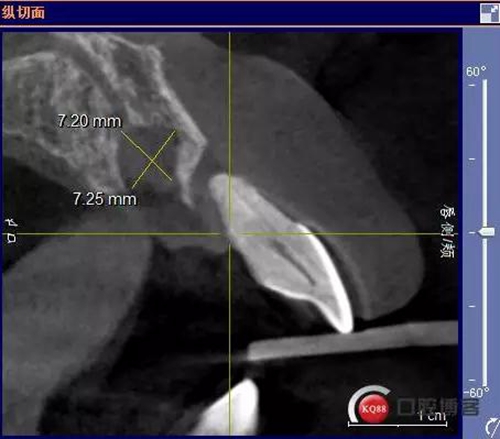

患者:王XX 年齡:42 上前牙松動(dòng)數(shù)年,從未做過(guò)任何處理,今來(lái)院就診;檢查:CBCT示上前牙區(qū)顎側(cè)一大小約7x7mm囊腫;治療計(jì)劃:即刻種植同期摘除囊腫

術(shù)前CBCT